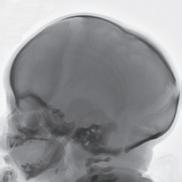

“When using standard MRI approaches, we are limited to brighter and darker shades of gray,” says MIITT co-director, Nicole Seiberlich, PhD, Research Professor of Cardiovascular Imaging and Associate Professor of Radiology. While radiologists are both skilled and experienced at reading and interpreting these images, introduction of a numerical measurement technique eliminates subjectivity, providing readers with specific data. “With our proprietary method, Magnetic Resonance Fingerprinting (MRF), radiologists can acquire quantitative data on multiple important properties simultaneously, which improves the accuracy of the diagnostic information. These quantitative tissue property maps include actual numbers that give experts reproducible and actionable results. It has been evaluated in brain, prostate, liver, cardiac, and musculoskeletal imaging.”

One of the many benefits of utilizing the MRF method as opposed to traditional MRI techniques is that it can be applied across vendors and machines to enable quantitative comparisons. “Before MRF, the shades of gray you received depended on all sorts of factors,” says Tom Griesler, MS, third year BME PhD candidate, whose research interests include MRF sequence design and optimization for brain and abdominal imaging. Results varied based on the series, settings, and manufacturer. Using MR Fingerprinting, numerical physical parameters enable comparison across time and space.